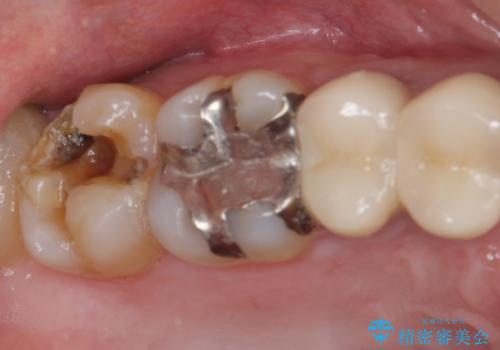

- 上の奥歯に装着されていた銀歯が外れてしまったとのことで来院された患者様です。

強い咬合力により銀歯と歯の間に隙間ができ、その隙間から虫歯となって外れてしまったと想像されました。

銀歯では歯と充填物の固さに違いがあり、再度外れてしまうリスクが高いため、固さが歯と近いゴールドインレー(PGAインレー)にて修復することとしました。